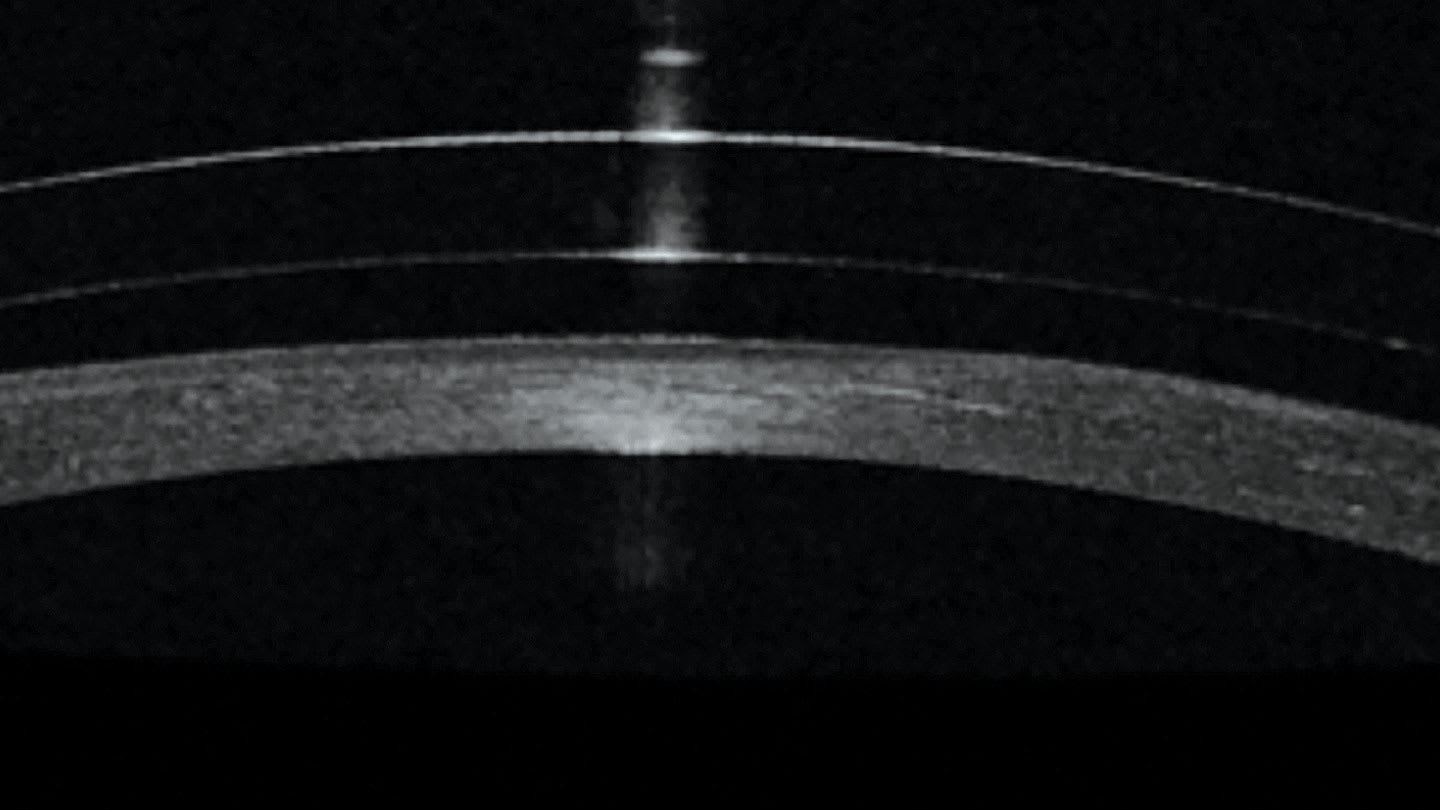

Selecting a base curve that is much steeper than the patient’s cornea will end up with an excessively plus tear reservoir between the lens and the cornea (Figure 1 vs Figure 2). A high minus over-refraction will result, and the resulting lens power will have to be ordered to allow the patient to see clearly. Conversely, if a base curve is flatter compared to the corneal curvature, a minus tear reservoir will be created, creating a need for a plus power to achieve clarity with the lens.